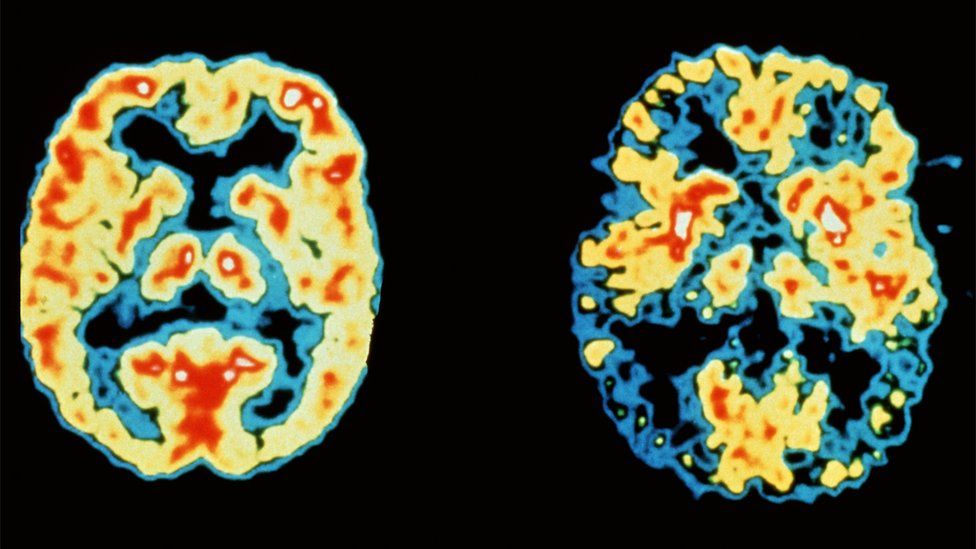

Një goditje në tru është një gjendje mjekësore serioze kërcënuese për jetën që ndodh kur furnizimi me gjak në një pjesë të trurit ndërpritet. Ato shkaktohen më së shpeshti nga mpiksja e gjakut. Shenjat që tregojnë se dikush ka një goditje në tru mund të përfshijnë rënien e fytyrës, gojës ose të dyjave në njërën anë dhe të folurit të paqartë dhe dobësinë e gjymtyrëve. Ndërsa demenca nuk është një sëmundje e vetme, por një grup simptomash të shkaktuara nga dëmtimi i trurit. Shenjat e gjendjes mund të përfshijnë humbjen e kujtesës, të tilla si kujtimi i ngjarjeve të kaluara shumë më lehtë se ato të fundit, ose probleme me të menduarit ose arsyetimin, ose të keni të vështirë të ndiqni bisedat ose programet televizive.

Pjesëmarrësit vetë-raportuan zakonet e tyre të pirjes së çajit dhe kafesë në fillim të studimit. Hulumtuesit më pas regjistruan numrin e njerëzve që patën një goditje në tru (2.8 për qind) dhe ata që zhvilluam sëmundjen e Alzheimerit ose demencën vaskulare (1.4 për qind). Ata zbuluan se pirja e çajit dhe kafesë lidhej me një rrezik më të ulët për të pasur një goditje ishemike (të shkaktuar nga një enë gjaku e bllokuar) dhe çmenduri vaskulare, në vend të një goditjeje hemorragjike (të shkaktuar nga një shpërthim i enëve të gjakut) ose sëmundjes së Alzheimerit, por ekspertë të jashtëm shpjegojnë se këto të dhëna nuk janë të mjaftueshme.